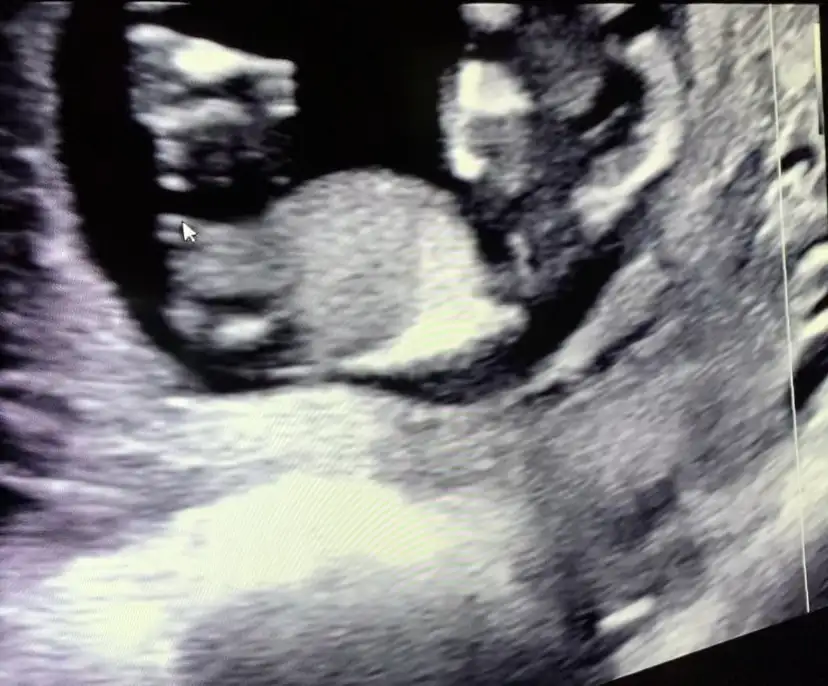

Ben de bakmanızı istesem 11+4 ultrason görüntüsü Ikra meyra

• IMG-20210510-WA0005.webp

19,4 KB · Görüntüleme: 79

• Screenshot_20210510-231802_WhatsApp.webp

11,5 KB · Görüntüleme: 86